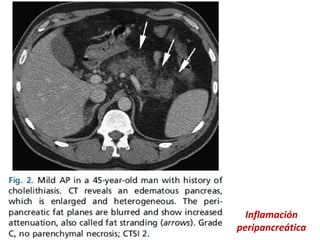

Inflamación

peripancreática